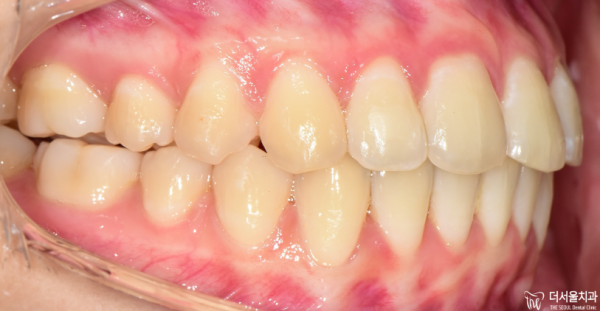

그리고 이렇게 측면에서 본디면 앞니가 앞으로

뻐드러져 있는 것을 확실히 확인할 수 있습니다.

돌출입의 형태라고 할 수 있는데요.

이 환자분께서는 '비발치교정'을 원한다고 하셨습니다.

저희 태평역치과 더서울치과에서는 인비절라인으의 클린체크시스템으로

시뮬레이션을 통해 비발치 교정이 가능한지 확인해 보았습니다.

And if you look from the side, the front teeth go forward.

You can definitely see that it's sticking out.

It's kind of a protruding mouth.

This patient said he wanted 'non-extract orthodontic'.

Taepyeong Station Dental Clinic The Seoul Dental Clinic uses Invisaline's clean check system.

I checked whether non-release calibration is possible through simulation.